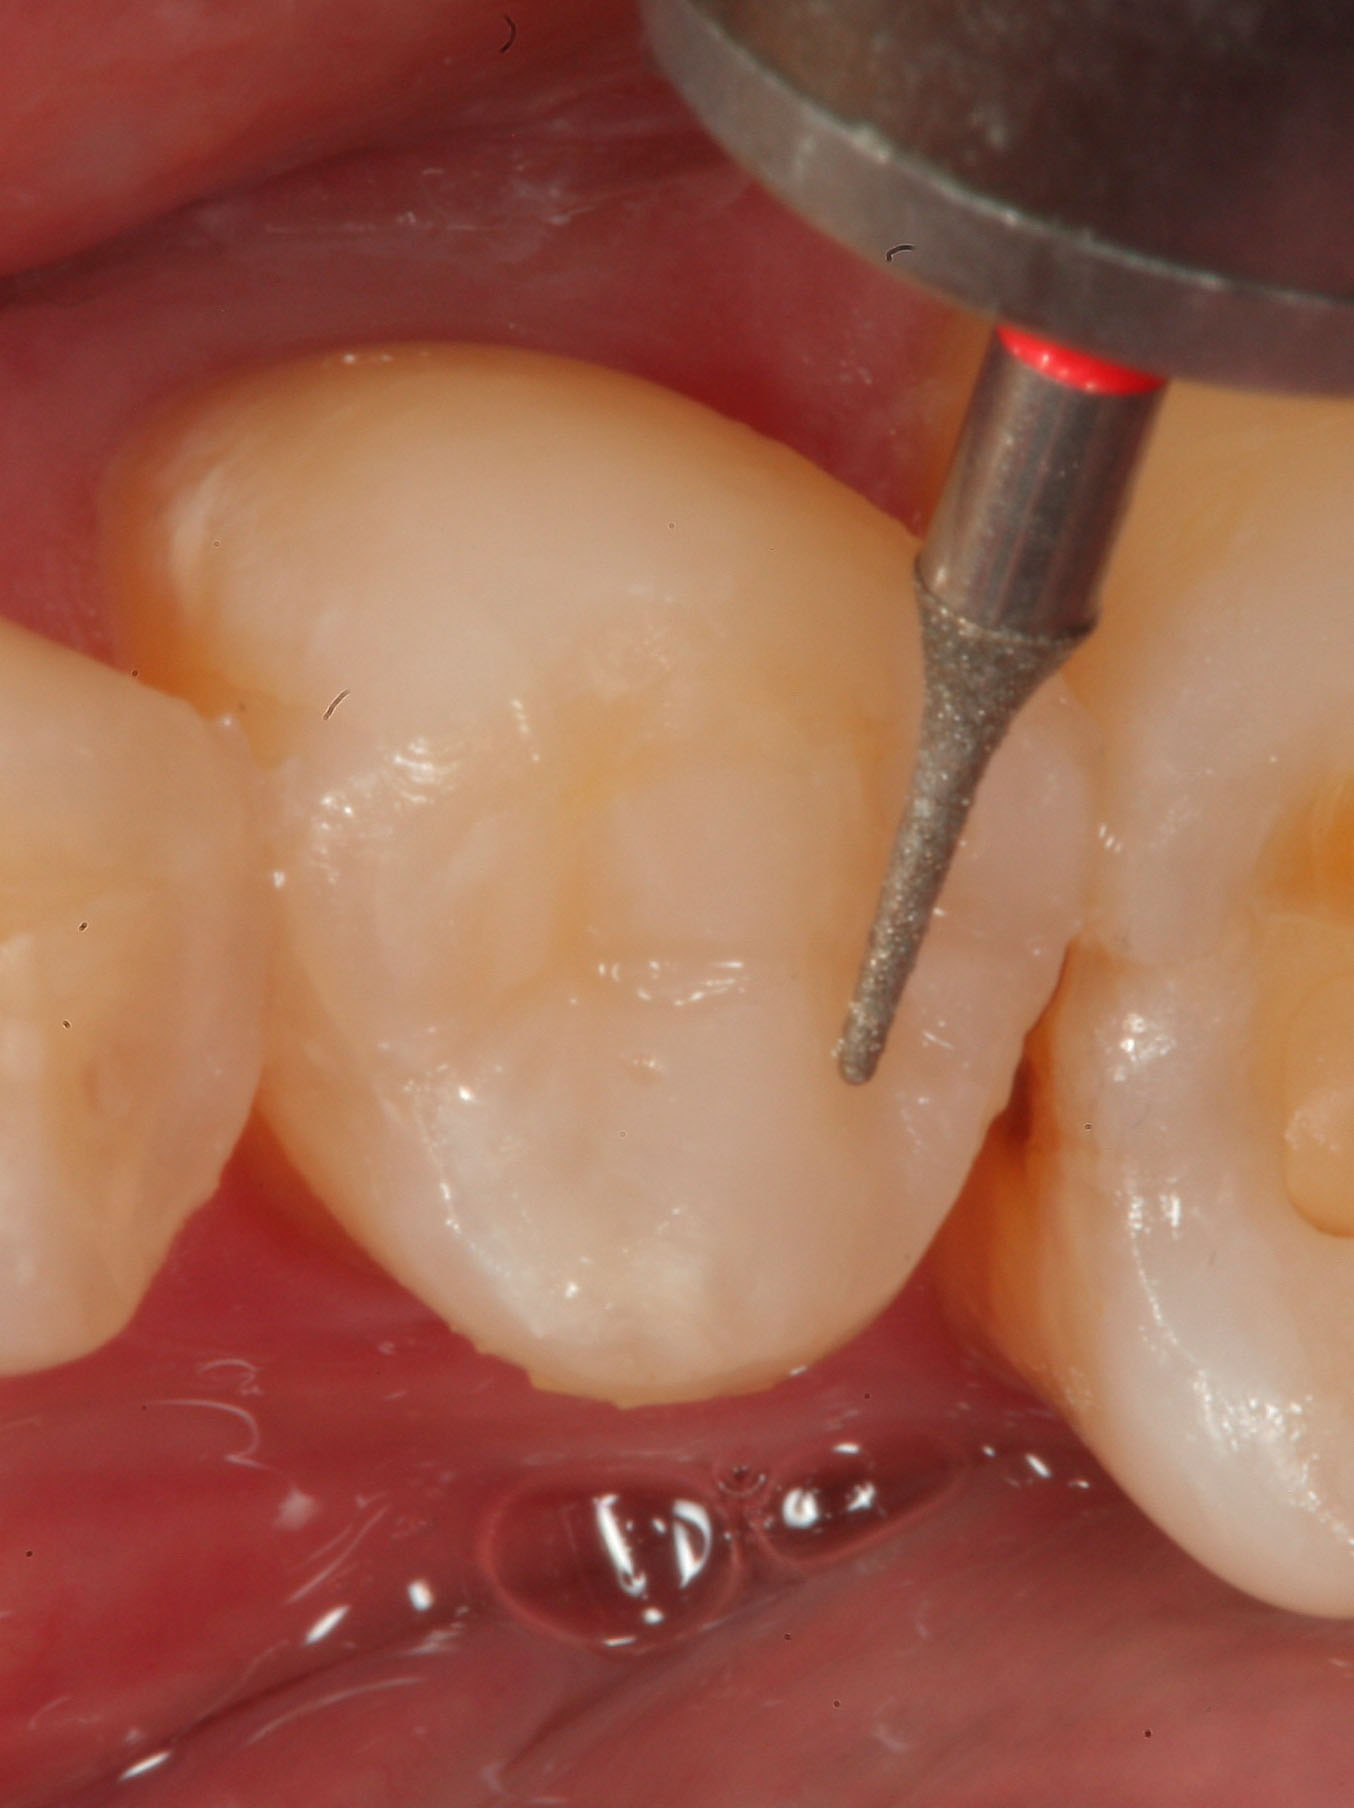

Fig 4. A 20-fluted carbide finishing bur is used to perform an occlusal adjustment on the occlusal restoration in tooth No. 31 before polishing.

Figure 4